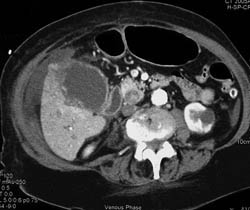

Acute Cholecystitis